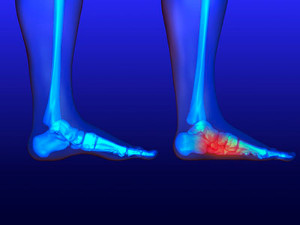

Common symptoms of stress fractures are pain and swelling near the weight bearing area on the injured bone. When initial x-rays are performed, it is possible that the fracture will not show up. However, once the stress on the area continues, the damage will increase, and the fracture will be severe enough to show up on an x-ray. Certain parts of the foot are more likely to develop stress fractures than others. Areas that typically have these fractures are: the metatarsals, the navicular bone, the calcaneus, tibia, and fibula.

It is important for you to be professionally diagnosed by a podiatrist if you suspect you have a stress fracture, because there are other injuries that can easily be mistaken for a fracture. Sprains, strains, shin splints, plantar fasciitis, and Morton’s neuroma can all easily be mistaken for stress fractures in the foot. Your podiatrist will likely ask you a series of questions to determine what type of pain you are experiencing. These questions will help your doctor identify whether you have a stress fracture.